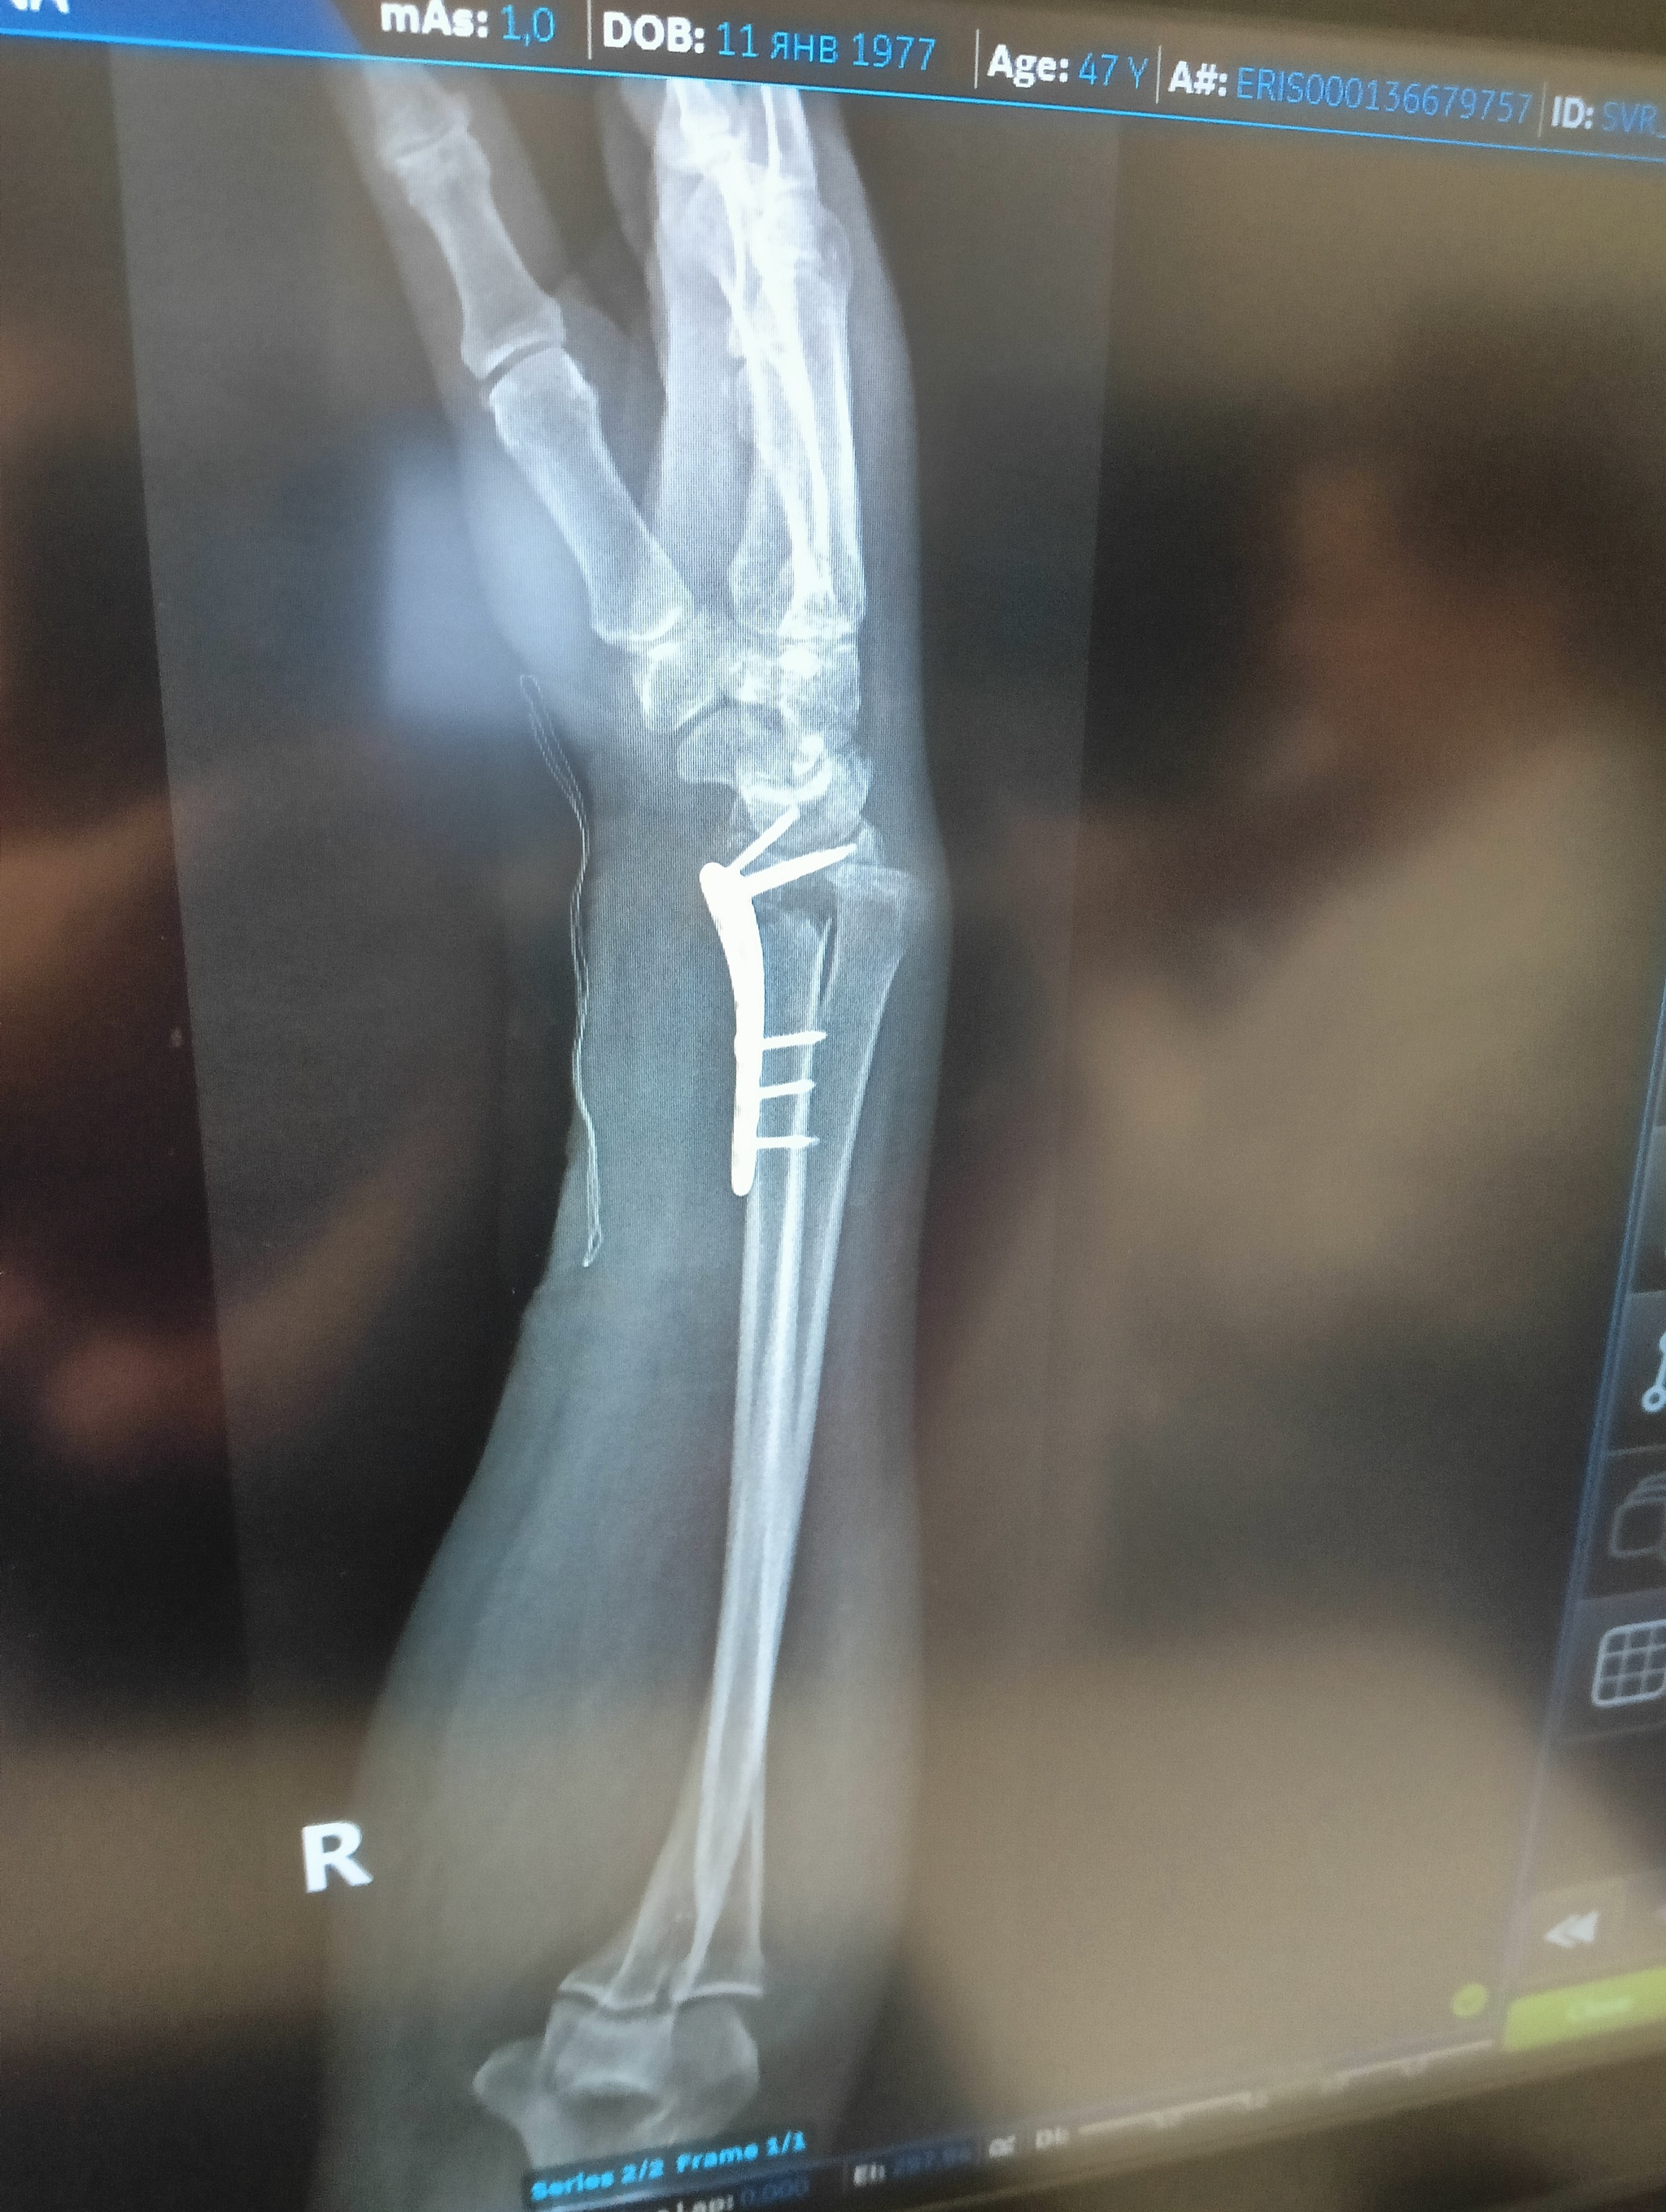

22 июля я неудачно упала и получила оскольчатый перелом дистального метафиза лучевой кости со смещением отломков более чем на 1/2 ширины диафиза. Открытый перелом шиловидного отростка локтевой кости. Была месяц в гипсе, но ничего не срослось. Диастаз костных отломков стал до 4 мм. Локтевая ушла в сторону на 5 мм. На 3 месяц после перелома мне сделали операцию, поставив титановую пластину. Сегодня сделала ренген и получила вот такой результат: Застарелый сомнительно консолидирующийся перелом дистального метафиза правой лучевой кости в условиях накостного МОС. Помимо отрыва шилообразного отростка локтевой кости, видно, имеется разрыв дистального радио-ульнарного сочленения.

Как я понимаю, Шиловидный отросток не прирос и стал болтаться, травмировав ткани внутри... Возможно, что это от реабилитации, я прохожу maps терапию для разработки руки, а может и просто, ведь рукой стараюсь пользоваться.

в ччетверг еду к хирургу, который меня оперировал. Но очень интересно мнение. Нужна ли тут операция и какая...

верхние ффото через 2 месяца после перелома, потом после операции и 2 нижние - сегодня